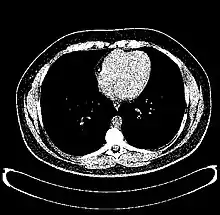

The Hounsfield scale (/ˈhaʊnzfiːld/ HOWNZ-feeld), named after Sir Godfrey Hounsfield, is a quantitative scale for describing radiodensity. It is frequently used in CT scans, where its value is also termed CT number.

HU-based differentiation of material applies to medical-grade dual-energy CT scans but not to cone beam computed tomography (CBCT) scans, as CBCT scans provide unreliable HU readings.[4]

Values reported here are approximations. Different dynamics are reported from one study to another.

Exact HU dynamics can vary from one CT acquisition to another due to CT acquisition and reconstruction parameters (kV, filters, reconstruction algorithms, etc.). The use of contrast agents modifies HU as well in some body parts (mainly blood).